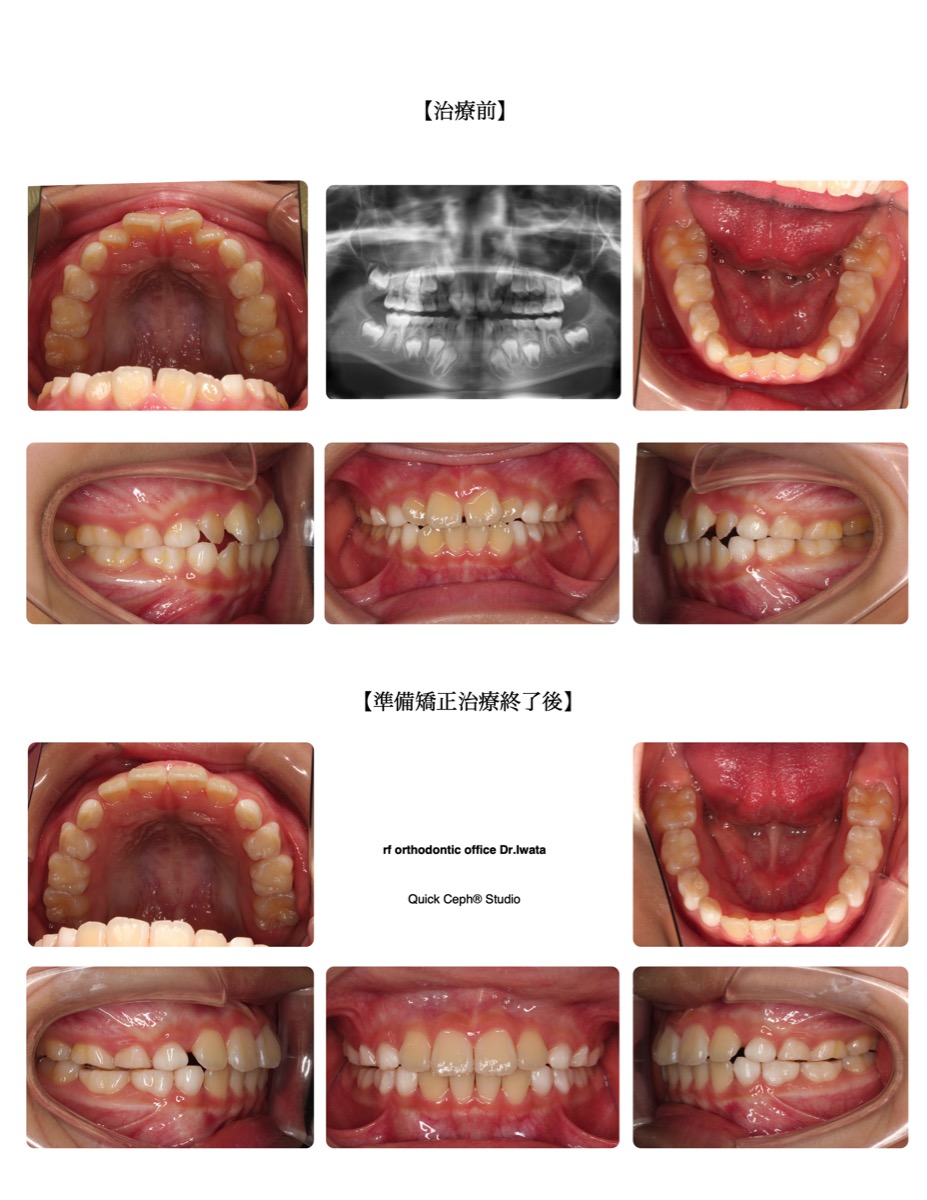

上顎前突症例 <過蓋咬合を伴う上顎前突に対してインプラントアンカーを併用した抜歯矯正治療>

【主訴】かみ合わせが深く、上の前歯が出ている。口元も綺麗にしたい。【主な症状】上顎前突 過蓋咬合 叢生【抜歯…